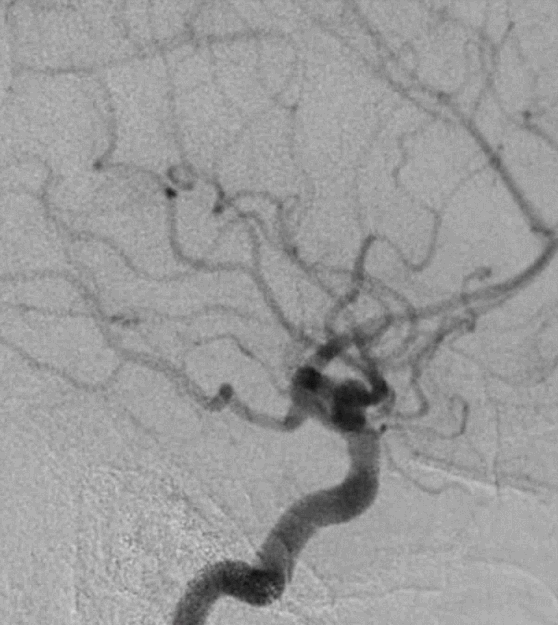

脑血管造影提示右侧颈内动脉颅内段多发动脉瘤(反主动脉弓)

脑血管造影提示右侧颈内动脉颅内段多发动脉瘤